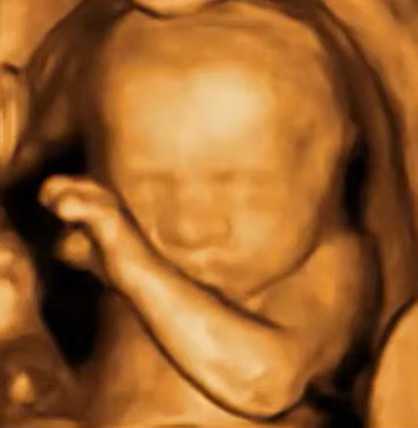

3D三维成像广泛应用于产科(看胎儿)、医美(看填充物)、甲乳、颈动脉、肌骨等。